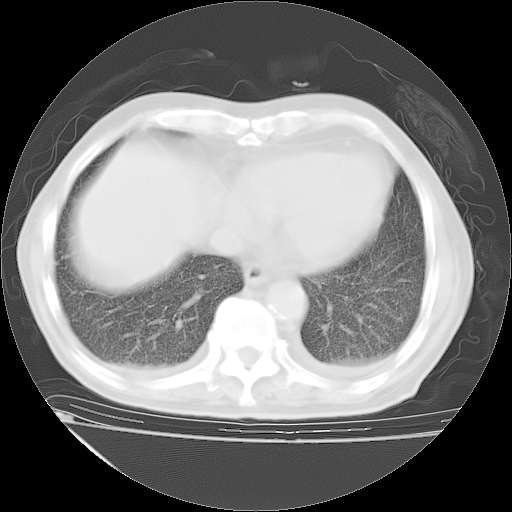

甲强龙80mg/日+抗结核治疗(异烟肼+利福霉素+乙胺丁醇)10天。复查肺部CT。

治疗10天肺部CT